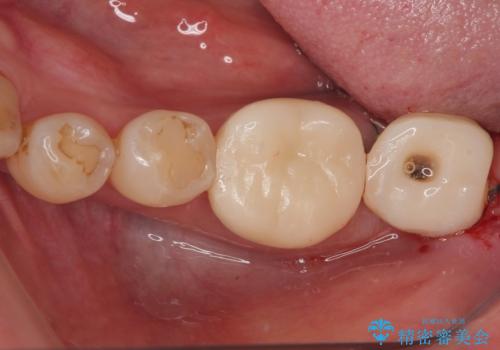

手前の歯は、適合の悪いクラウンを最後方歯と同時にオールセラミッククラウンにて補綴治療を行うこととしました。

骨の高さが不十分であったため、インプラント強度を維持しながらも高さの小さいインプランを使用しました。